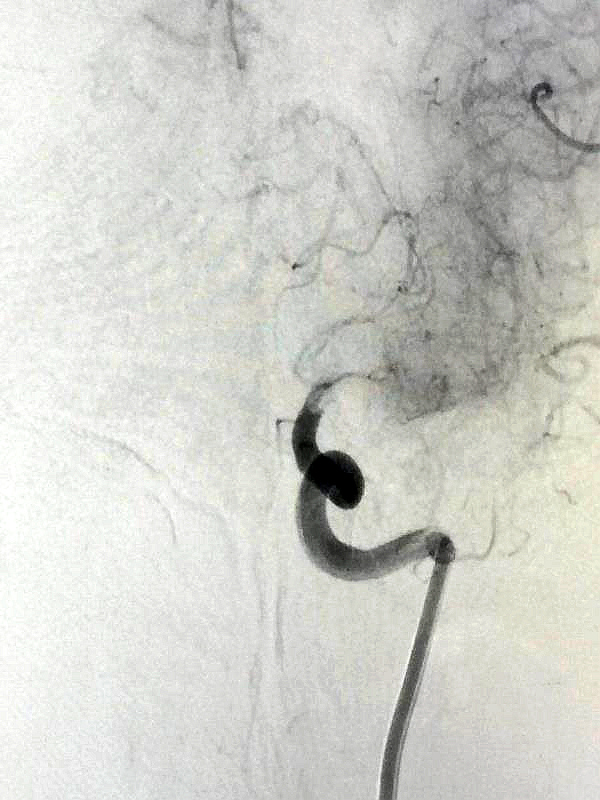

第一幅:荒漠中一棵枯樹,由于年事已高,加病蟲害侵蝕,已不見往年的繁華,幾乎只剩孤零零的樹干,一片悲涼的景象。站在畫前,不禁讓我想起了元代馬致遠(yuǎn)的《天凈沙·秋思》——枯藤老樹昏鴉,小橋流水人家,古道西風(fēng)瘦馬。夕陽西下,斷腸人在天涯。

其實(shí),這兩幅畫并非人工繪制,而是來自濱州市人民醫(yī)院介入手術(shù)室血管造影機(jī)拍攝的影像。